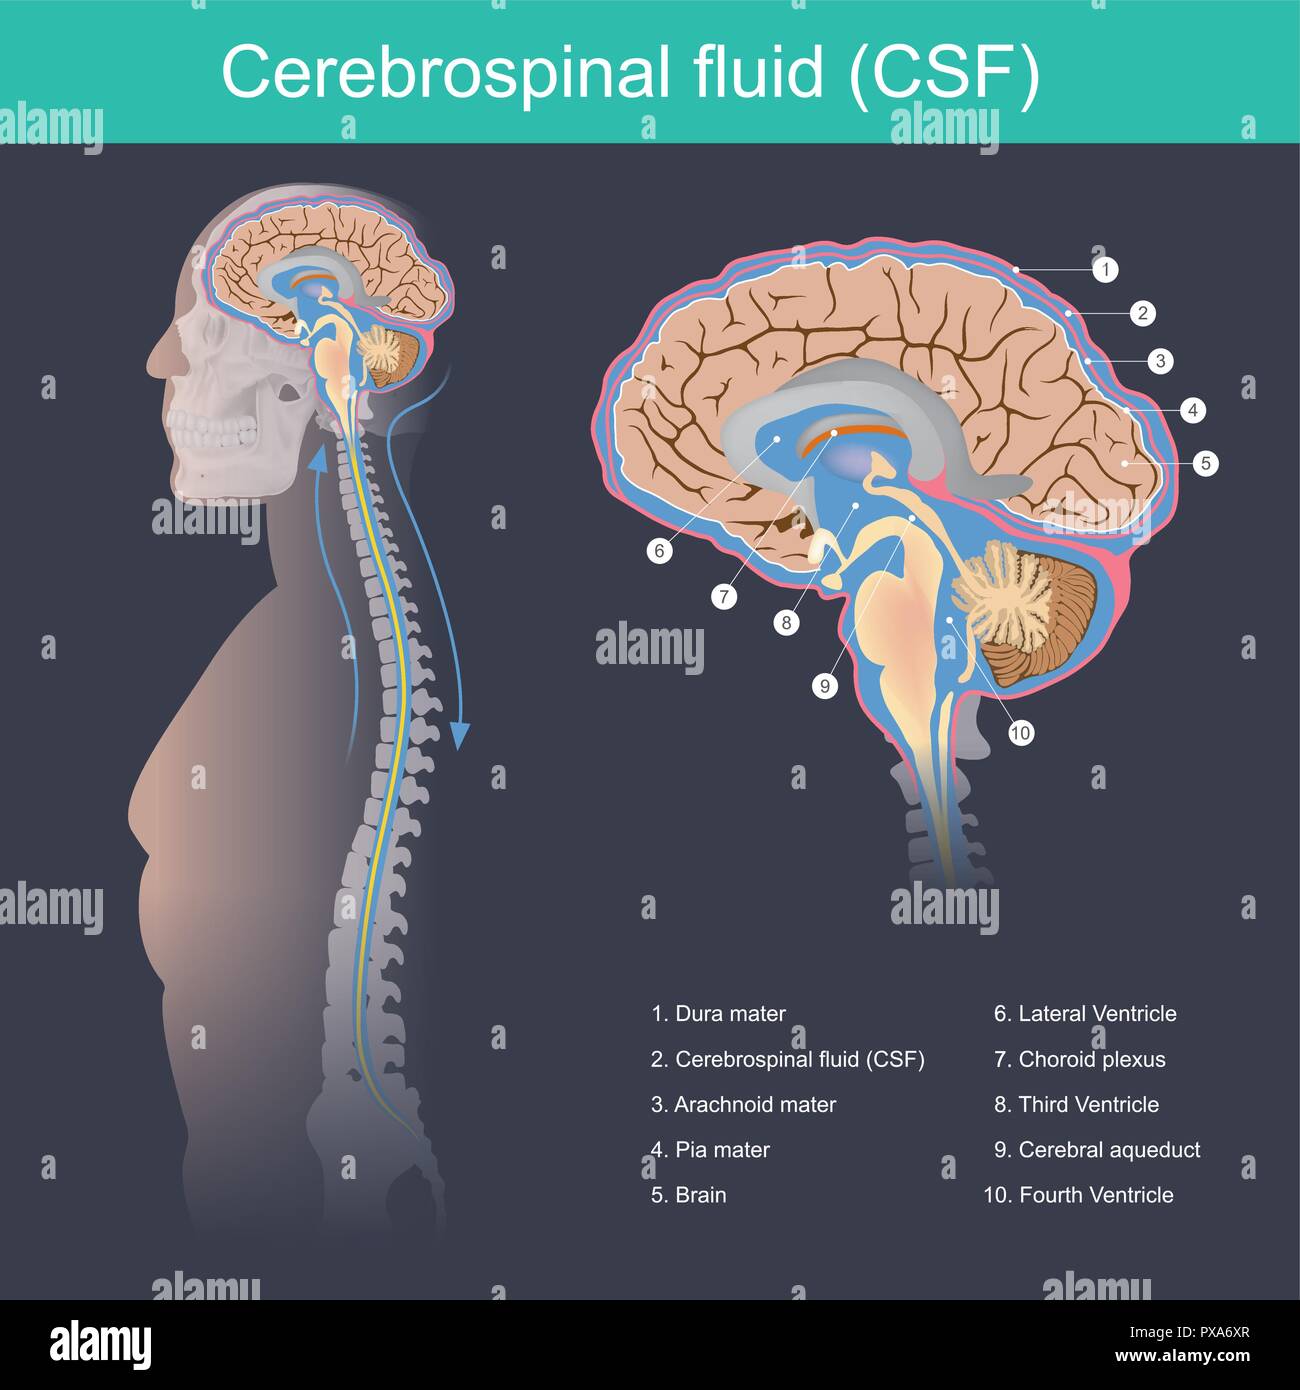

RFPXA6XR–Der zerebrospinalen Flüssigkeit (CSF) ist das Gehirn und das Rückenmark von Auswirkungen schützt, eliminiert Abfälle aus dem Gehirn und Rückenmark, und hilft Giftstoffe im

RM2AWFNN9–Menschliche Anatomie, einschließlich Struktur und Entwicklung und praktische Überlegungen d in einem sagittalen mesialen Abschnitt (Abb. 910) wird jede dieser Teilungen als mit einem Teil des Systems der Kommunikation von Räumen verwandt angesehen, die als die dritten Ventrikel des Lateralands, der Aquädukt von Sylvius und der vierte Ventrikel die oben genannten Gehirnhemisphären ausdehnen. Durch den Hirnstamm und unter dem Kleinhirn bis zum zentralen Kanal des Rückenmarks. Da die lateralen Ventrikel zwei innumerieren, ist die Theirstellung im Zusammenhang mit den Gehirnhemisphären, in denen sie liegen, lateral zum m

RM2AN4TWY–Handbuch der allgemeinen, beschreibenden und pathologische Anatomie (Band 2). Ventrikel, ein. Ventrikel des Kleinhirns, b. Aquädukt von Sylvius, C. Dritten Ventrikel, d. Lateralen Ventrikel, 1. Vordere Horn, 2. Hintere Horn, 3. Absteigend Horn, II. Textur, III. Gewicht, IV. Konsistenz, Kap. Iii. Umhüllt des Gehirns. Abt. Ich. Pia - mater, I. des Rückenmarks, II. Von Hirn, ein. - Externe Pia mater, b. Interne pia-mater, ich. Choroid Plexus des vierten Ventrikel, ii. Choroid Plexus des Großhirns, Art.ii.Apert-syndrom Membran, Art. hi. Dura-mater, I. spinalen Dura-mater, II. Zerebrale Dura-mater

RM2CDFE0C–. Elemente der physiologischen Psychologie; eine Abhandlung über die Aktivitäten und die Natur des Geistes, aus der physischen und experimentellen Gesichtspunkten. ide,die corpora quadrigemina. Die Kavität des Neuralrohres bleibt hier klein und bildet das Aquädukt, das den Viertmit dem dritten Ventrikel verbindet. Im Zwischenhirn dehnt sich das Aquädukt in den dritten Ventrikel aus; und hier wird wieder die dorsale Wand des Tubus zu einer breiten, dünnen Membran, die in den Ventrikel gefaltet und Blutgefäße mit sich trägt. Während die zerebralen Hemisphären ihr enormes Wachstum durchlaufen, dehnt sich die Kavität mit ihnen aus, andrema